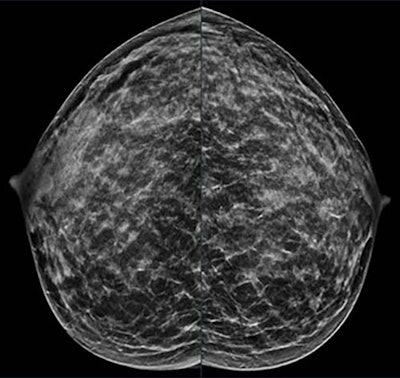

A 40-year-old patient presents for routine screening with a family history of the paternal grandmother, age 55. Extremely dense breast tissue is noted on mammography right and left craniocaudal view.RSNA

A 40-year-old patient presents for routine screening with a family history of the paternal grandmother, age 55. Extremely dense breast tissue is noted on mammography right and left craniocaudal view.RSNA